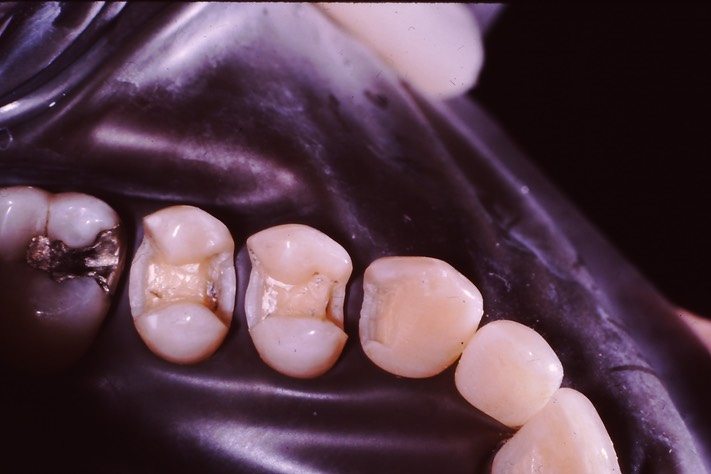

Dr. May Chang’s cases

March 1, 2012